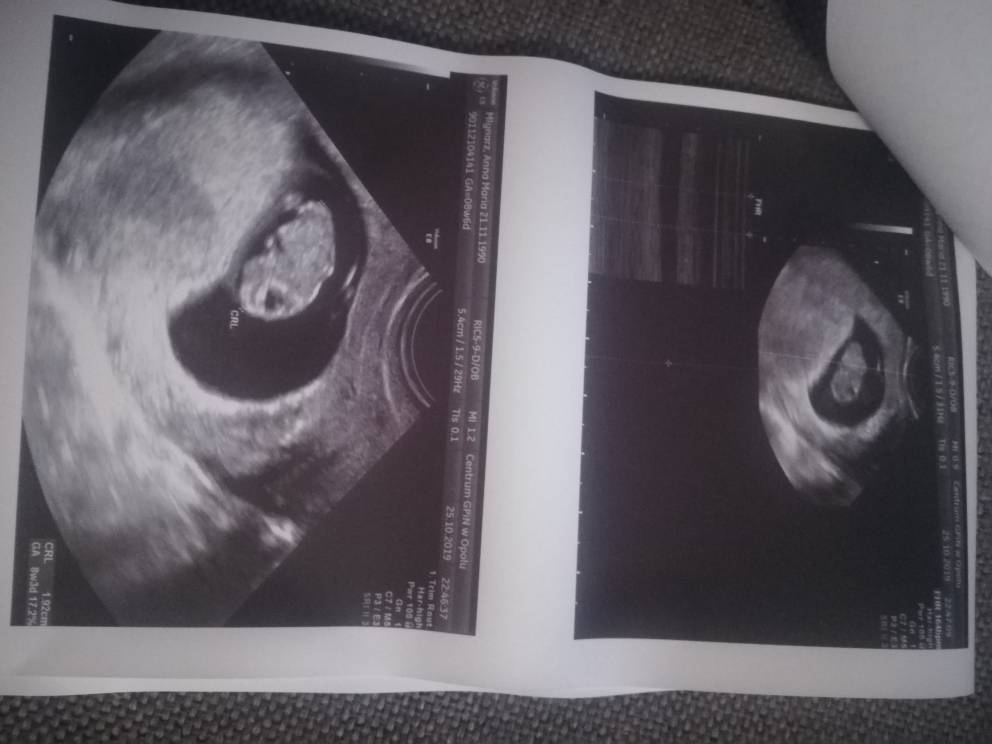

Właśnie wróciłam, trochę się wyczekałam. Wszystko jest ok!!! Przyjął mnie bardzo niemiły lekarz, który generalnie dał do zrozumienia, że po co przyjechałam. Szkoda gadać. Zbadał wziernikiem, nie było żadnej krwistej wydzieliny. Na usg wszystko ok, dzidziuś ma się dobrze [emoji3590][emoji3590][emoji3590] Na jajniku sprawdzał, bo mu wspominałam o torbieli i wpisał, że jest hipoechogenny pęcherzyk. Nie wiem, czy tak nazwał torbiel niewiele co mówił... [emoji58] Ogólnie powiedział, że jak coś złego się dzieje, to pojawiają się skrzepy krwi. Jak mówiłam o galarecie to powiedział, że wydzielina w ciąży może mieć różny charakter. I że czop śluzowy jest dopiero w połowie ciąży. A to ciekawe... No nic. Nie będę się gburem przejmować. Najważniejsze, że wszystko jest dobrze [emoji3590][emoji3590][emoji3590] Załączam zdjęcie maluszka, FHR 168/min [emoji3590]

Dzidziuś [emoji3590]

IMG_20191025_234755.jpeg